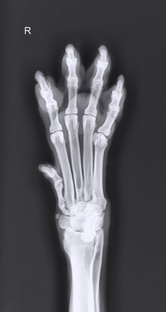

Рентгенологические укладки грудных конечностей собак и кошек.

Медиолатеральная проекция плеча Центрирование лучей На плечевой сустав. Расположение пациента и настройка рентгеновского луча Пораженная конечность прилежит к кассете, пациент должен находиться в боковом лежачем положении. Одна конечность вытянута краниально и вентрально к грудине, чтобы предотвратить наложение. Другую вытягивают в каудодорсальном направлении. Шея вытянута дорсально. Грудина слегка повернута. Настройте рентгеновский луч, чтобы включить дистальную треть лопатки и проксимальную треть плечевой кости...